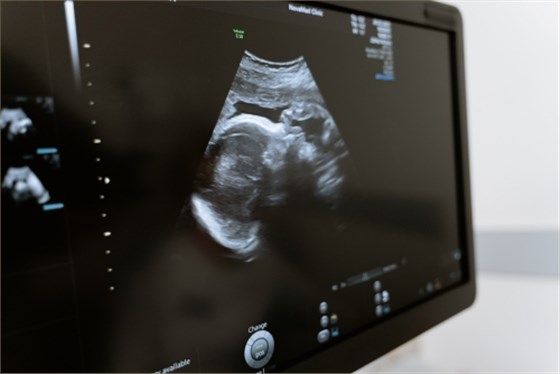

上肢血管超聲檢查是通過超聲檢查血管壁、血管內(nèi)血流情況的技術(shù)。一般情況下,上肢血管超聲檢查可用于診斷動脈硬化、靜脈狹窄、動靜脈瘺、血栓閉塞性脈管炎、靜脈血栓形成等疾病。

1、動脈硬化:動脈硬化是一種非炎癥性病變,隨著年齡的增長,動脈壁會開始脂質(zhì)沉積、纖維組織增生,最終導(dǎo)致動脈硬化。通過上肢血管超聲檢查,可以明確動脈硬化的程度,測量動脈內(nèi)中膜厚度,觀察動脈斑塊的形態(tài),幫助診斷動脈硬化;

2、靜脈狹窄:靜脈狹窄一般是由于血液受阻所致,可能由于血液黏稠度高、血流緩慢等因素所致。通過上肢血管超聲檢查,可以判斷狹窄的程度和位置,明確是否為靜脈狹窄;

3、動靜脈瘺:動靜脈瘺是一種先天性疾病,是由于先天性發(fā)育異常或后天性損傷導(dǎo)致動靜脈之間的通道出現(xiàn)異常,血液可能會由此進(jìn)入鄰近器官的病灶中。通過上肢血管超聲檢查,可以觀察到血管是否出現(xiàn)明顯的空洞,明確是否存在動靜脈瘺;

4、血栓閉塞性脈管炎:血栓閉塞性脈管炎是由于小動脈痙攣、出現(xiàn)血栓導(dǎo)致局部缺血而引起。通過上肢血管超聲檢查,可以觀察到局部血管內(nèi)膜增厚,內(nèi)膜不光滑,有斑塊形成,并且可以觀察到局部的血管管腔狹窄;

5、靜脈血栓形成:靜脈血栓形成是由于長期臥床休息、創(chuàng)傷等因素,導(dǎo)致血液高凝狀態(tài)、血管損傷等因素所致。通過上肢血管超聲檢查,可以觀察到局部血管內(nèi)形成血栓,并且可以觀察到血管內(nèi)有血流信號,可以診斷靜脈血栓形成。